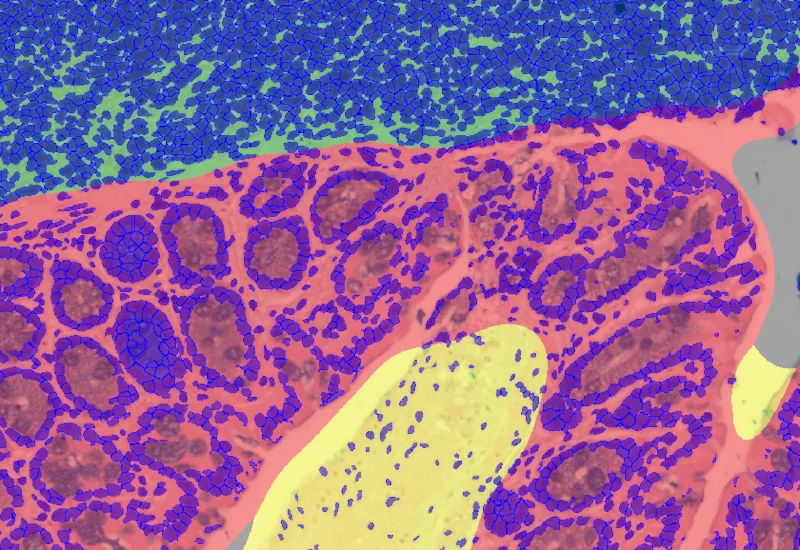

The IF Swiss Roll App segments tissue into subclasses (e.g., mucosa, follicles, connective tissue), detects nuclei, and identifies phenotypes via IF stains.

The IF Swiss Roll App allows for detection of the swiss roll, and the segmentation into different subclasses (mucosa, immune cell follicles, connective tissue, background). Further it detects nuclei and identifies phenotypes based on specific IF stains. The App outputs area (µm2) of detected tissues/tissue classes, count of total cells as well as in each detected area. Count and % of specific phenotype detected in total as well as in the tissue classes.

Nuclei and Phenotype detection